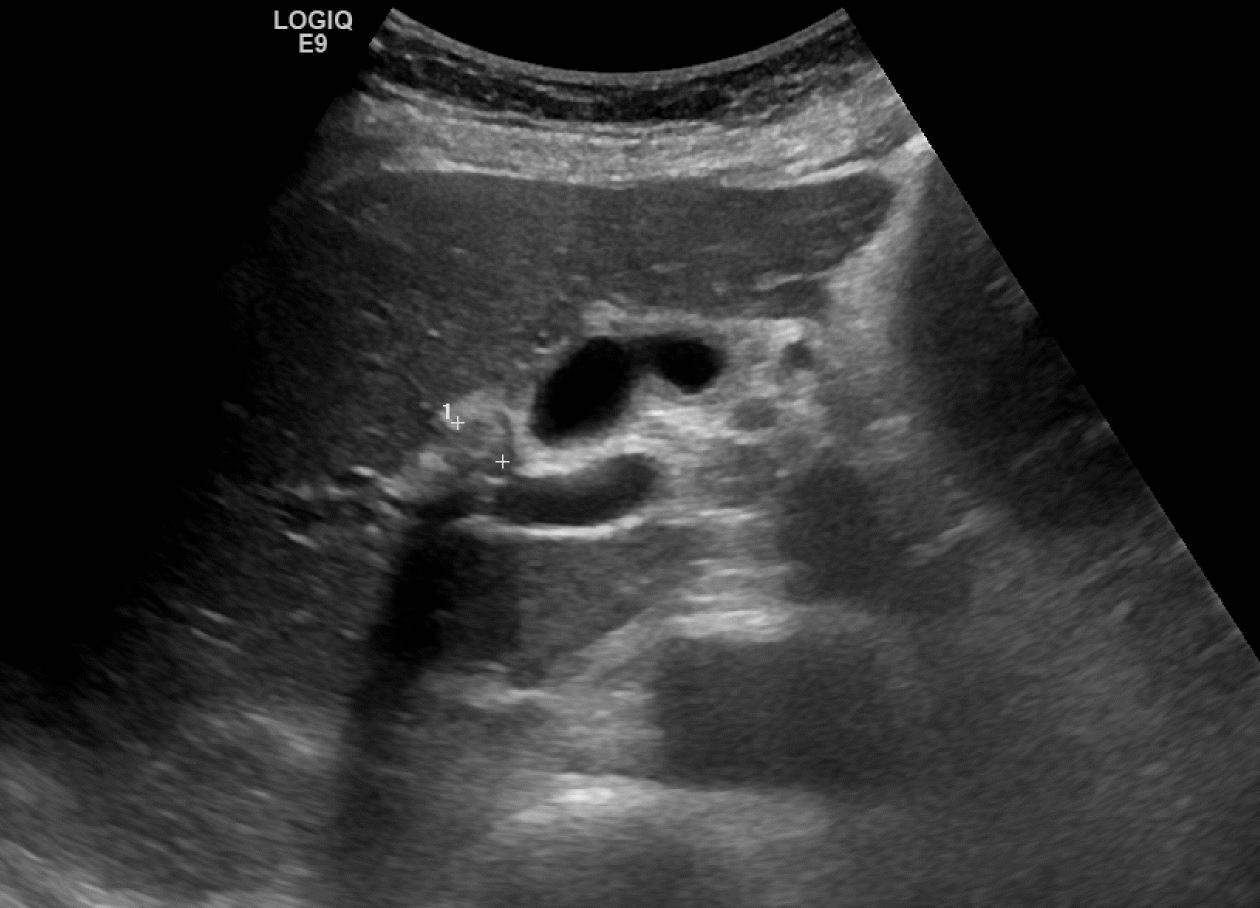

CT에서 보이던 우측 간내담관결석이 보이며, 담관의 확장이 같이 확인됩니다.

CT영상에서는 전혀 안보이던 총수담관 내 결석이 확인됩니다. 그리고, 결석 근처의 총수담관 벽이 불규칙하게 두꺼워져 보입니다.

같은 총수담관내 결석을 횡단면 스캔영상으로 확인했습니다. 뚜렷한 후방에코음영을 동반한 결석을 확인할 수 있습니다.

총수담관의 아래쪽 끝부위를 종단면스캔한 영상입니다. 앞서 보였던 담관결석과 총수담관의 갑작스러운 폐쇄가 보입니다. 앞서 보였던 총수담관 벽이 두꺼워지고 총수담관의 급격한 폐쇄는 근처에 경계가 불분명한 침윤성 병변의 가능성을 제기할 수 있는 소견입니다. 즉, CBD cancer의 가능성까지 의심해볼 수 있는 영상소견이지요.

이처럼 CT에서는 전혀 확인할 수 없었던 간외담관의 결석 및 담관암 의심소견을 초음파 영상에서는 비교적 쉽고 명확하게 확인할 수 있는 사례였습니다. 실제 담관의 확장이 있는 경우 위와 같이 CT에서는 전혀 보이지 않는 병변을 초음파영상에서 확인하는 경우가 꽤 흔합니다. 이러한 경험을 많이 하지 않은 분들이 CT의 유용성을 마치 만능에 가까운 것처럼 착각하는 경우가 있습니다만, 실제로는 이번 사례처럼 그렇지 않습니다.

간혹 초음파영상이 검사하는 사람의 경험과 노력에 따라 민감도나 특이도 편차가 크기 때문에 불안을 느껴서 CT를 초음파영상보다 더 신뢰하게 되는 경우가 있는데, CT나 초음파 영상 모두 어느 한쪽을 완전히 대체할 수 없는 영상검사라는 점을 잊어선 안됩니다.